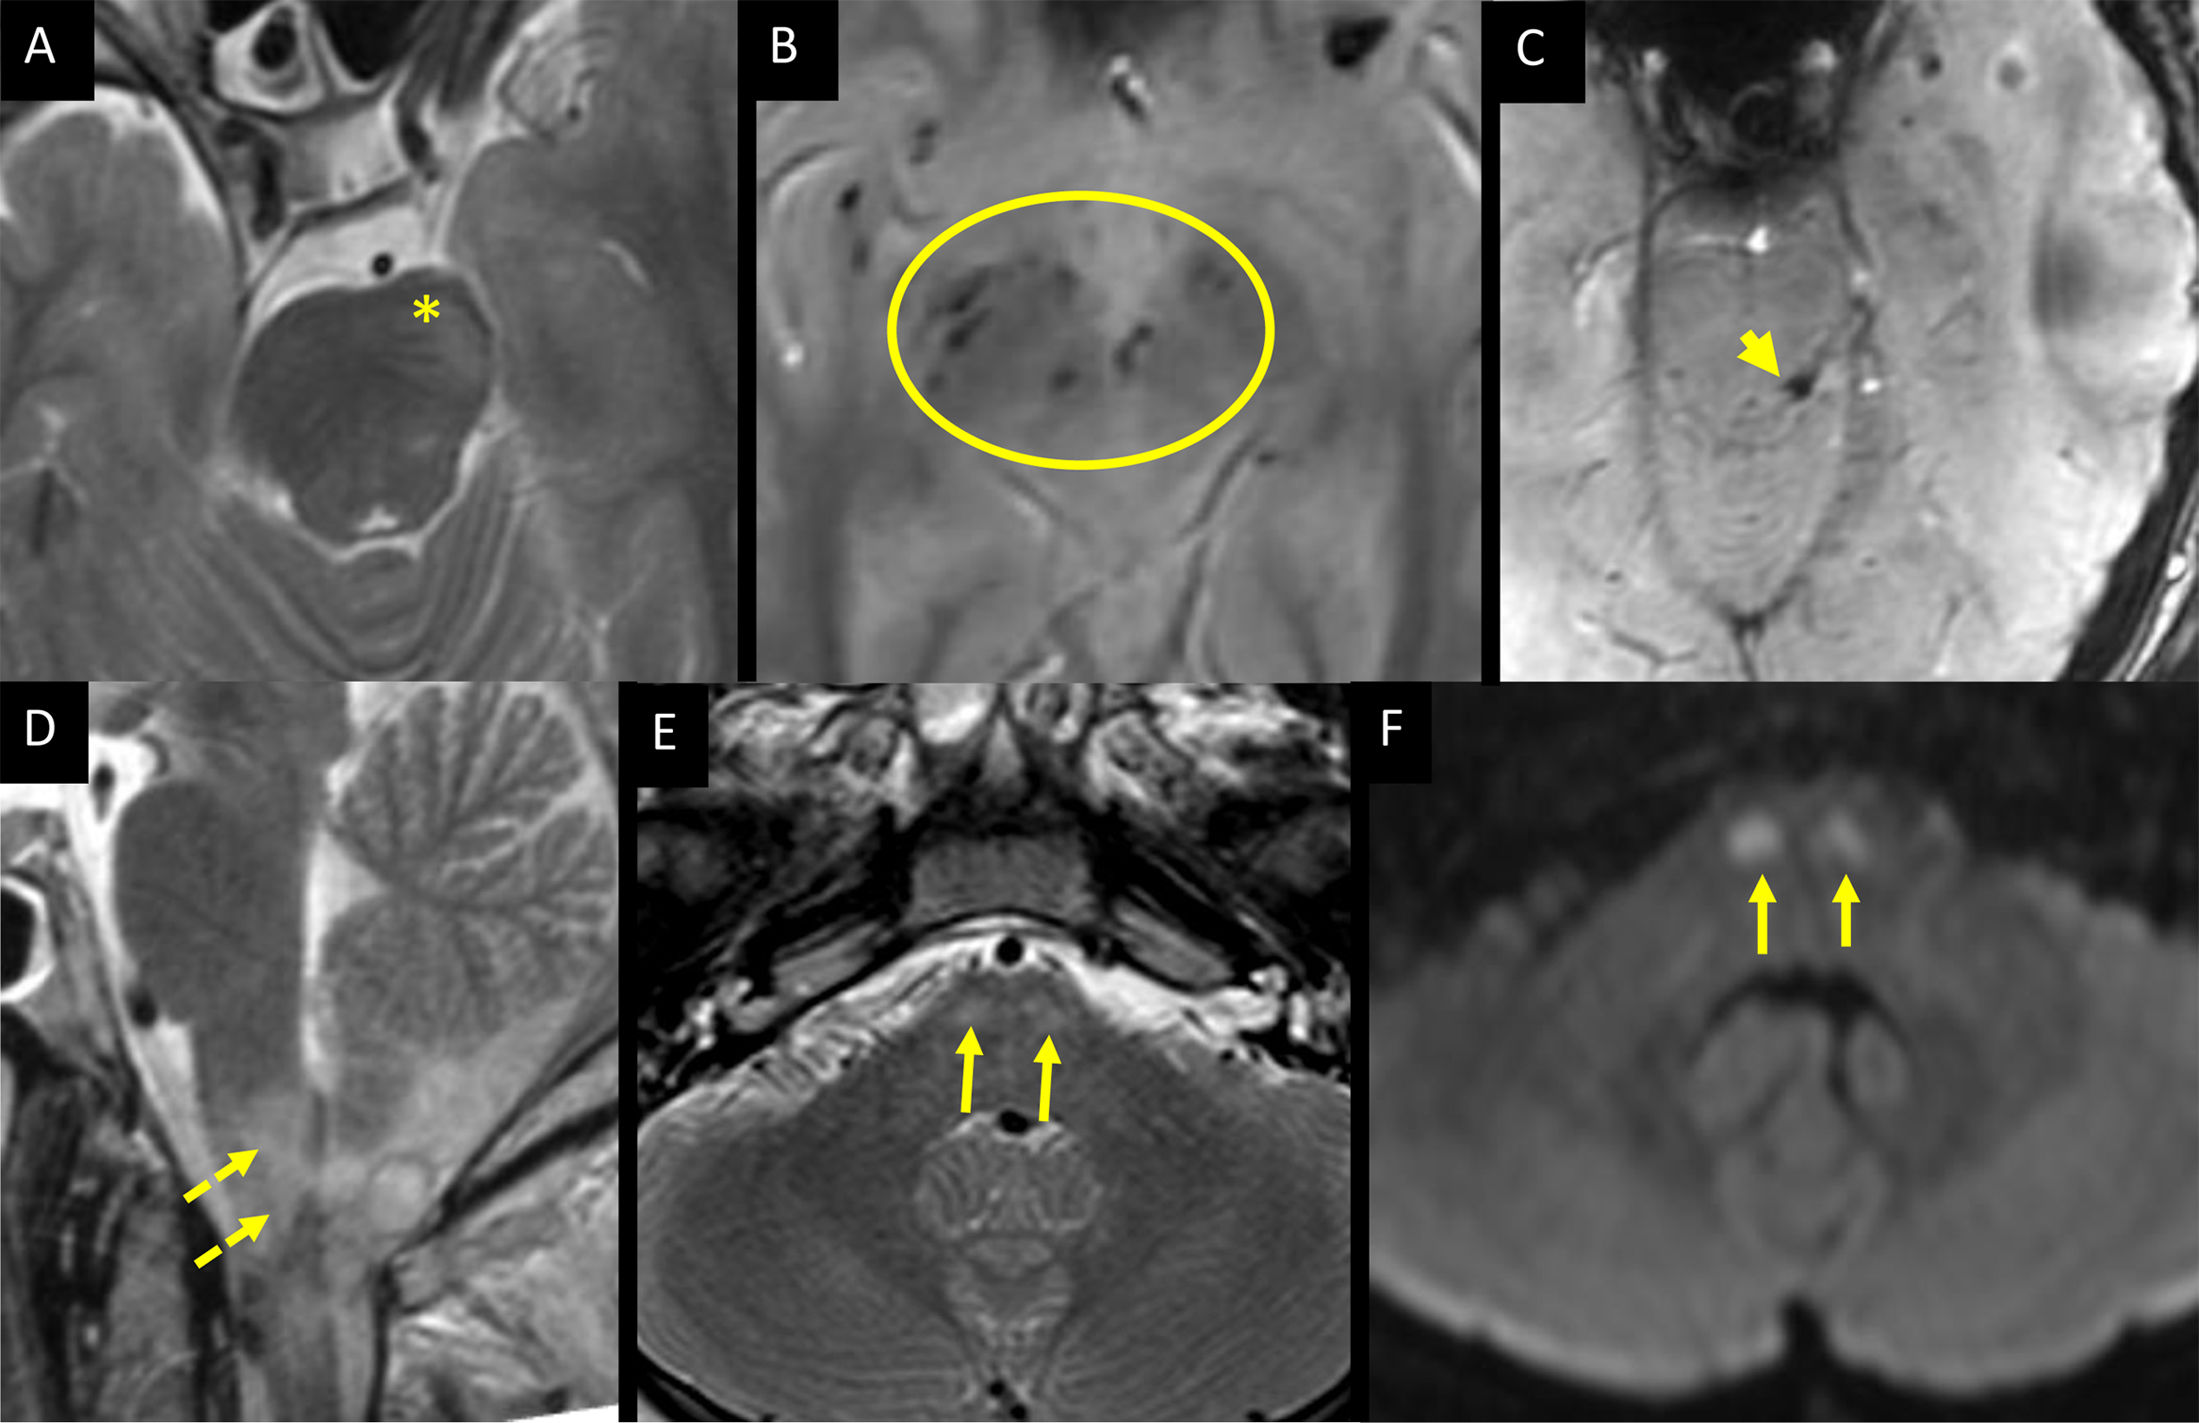

Traumatic brain injury (TBI) is the leading cause of morbidity and mortality in young patients. The Marshall classification predicts six-month mortality and divides severe TBI patients into six groups based on CT findings in the acute phase of trauma. MRI also has prognostic value because it detects 30% more traumatic lesions, especially brainstem injury and diffuse axonal injury. Diffuse axonal injury occurs in three different anatomical areas, graded according to severity, and the greater the trauma, the deeper the brain involvement extends. Traumatic brainstem injuries with the worst prognosis are those of posterior location, with bilateral or haemorrhagic involvement. This article analyses the prognostic value of CT and MRI in the assessment of severe TBI and describes the main intracranial traumatic injuries.